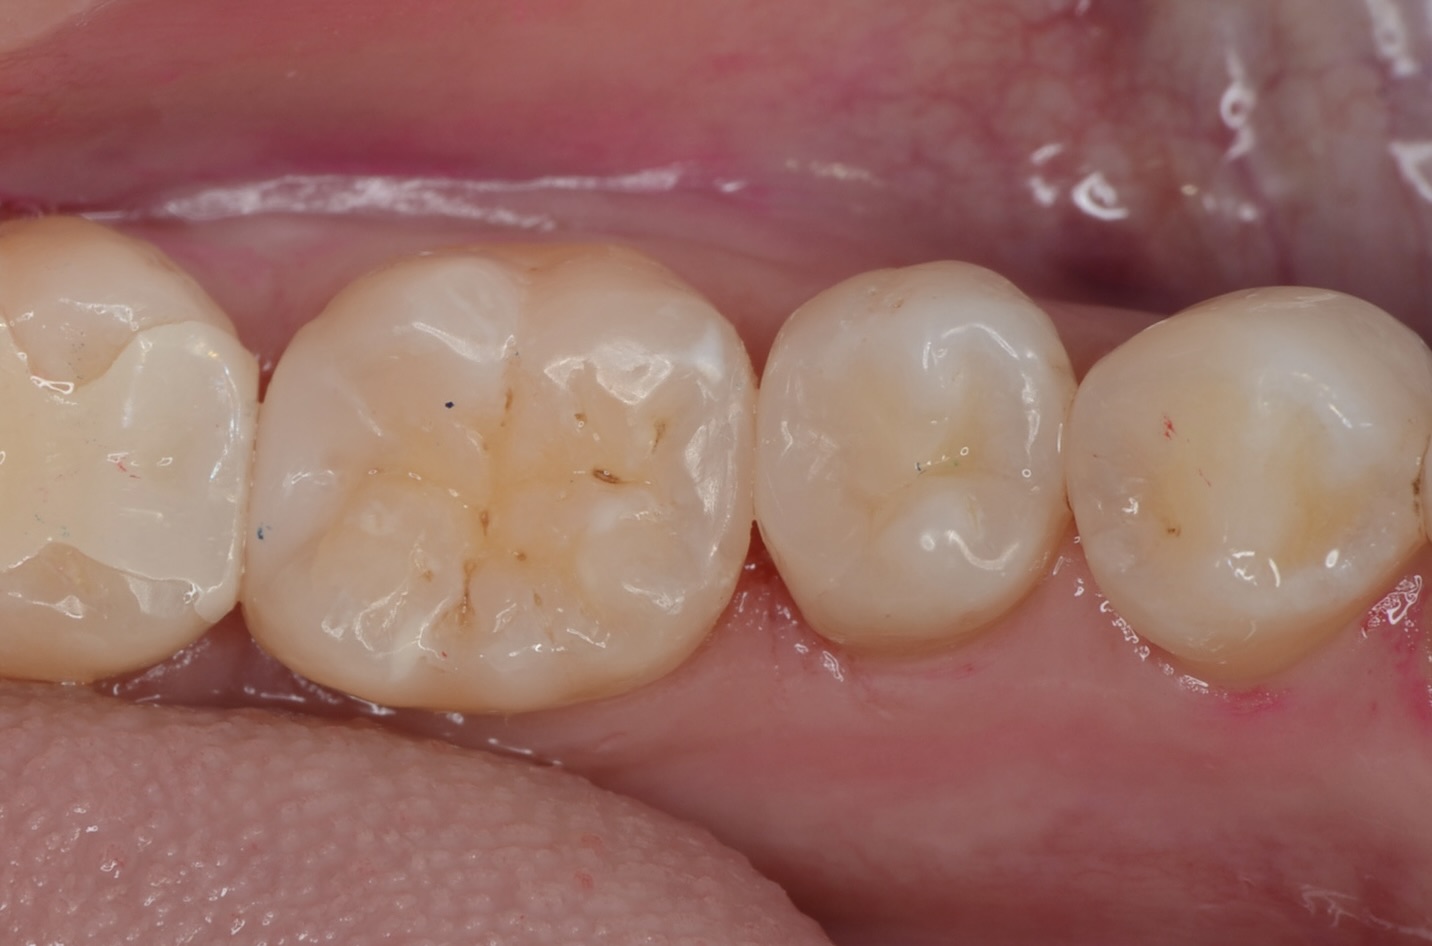

硎磨

自然な見た目に仕上がりました。噛み合わせも問題ありません。本当の審美歯科とは、見た目の美しさ・機能・清掃性が伴って成立します。 -

頬側面観

-

舌側面観